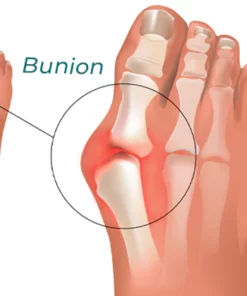

When you have bunions or overlapping toes, long days on your feet can be quite painful. By entering and soothing the underlying tissue to lessen hurting and discomfort, the RASSMAM™ BunionOut Relief Patch can assist in providing that pain relief in a natural way.

- This patch aids in stimulating the lymphatic system, which helps lymph fluids move throughout the body and improve circulation, as well as reducing pain and swelling, accelerating metabolism, and easing stiff joints.

- RASSMAM™ BunionOut Relief Patch are made to straighten your big toe and put it back in its proper place. It not only relieves your toe from the pain, swelling, and pressure brought on by bunions, but it also aids in reducing the bunion so that the joint won’t become misaligned once again. Relieve pain and overlapping toes without surgery.